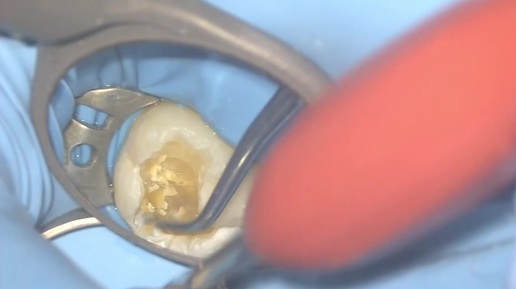

Клинический случай лечения глубокого кариеса